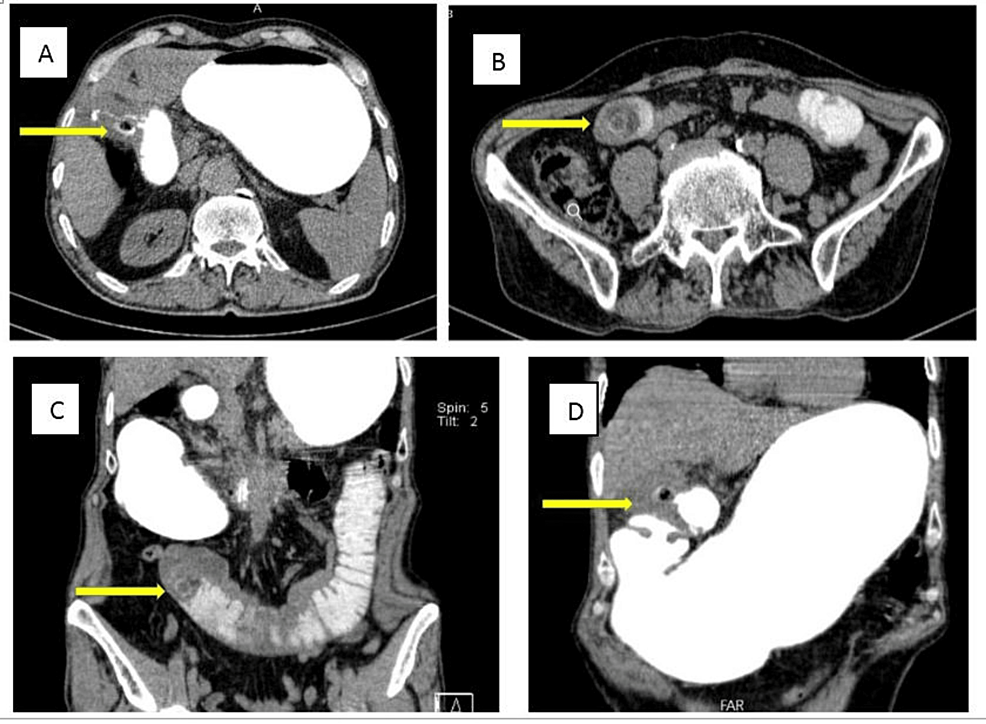

Upright abdominal X-ray showed mildly dilated small bowel loops (Figure 1). An abdominopelvic CT scan with oral contrast was performed. Findings were compatible with gallstone ileus: dilated duodenal and jejunal loops, fistulous tract between gallbladder wall and duodenal bulb, oral contrast leakage to gallbladder lumen, obstructing layering gall bladder stone in the jejunum, and at least two other stones in the gall bladder (Figure 2).

Inflammatory changes, pressure erosion, and ischemia of the gallbladder wall could lead to biliary-enteric fistula in patients with a long-standing history of gallstone disease. Cholecystoduodenal fistula is the most common manifestation (32.5-.96.5%) [3] as shown in our case, which was well demonstrated in the CT scan.

Lassandro et al. found that the Rigler’s triad is observed in 14.8% of cases via plain abdominal radiography, 11.11% of cases on ultrasound examination, and 77.78% on abdominal CT scan [14]. In our patient, the Rigler’s triad was present on the CT scan, but it was not clearly visible on the abdominal X-ray. A correct preoperative diagnosis has been reported only in 50% of cases. Sometimes, gallstone ileus is diagnosed during surgery in patients with an unknown cause of small bowel obstruction [17].